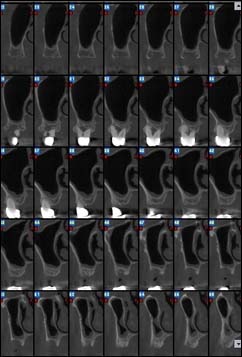

EXAMENS TOMOGRAPHIES VOLUMIQUES TYPE SCANNER OU CÔNE BEAM :

Dernière technologie à notre disposition, cette technique permet de voir en 3 dimensions des images de votre bouche et de mettre en évidence des pathologies ou des anomalies que les autres techniques ne permettent pas d’objectiver.

Reconstruction coronale